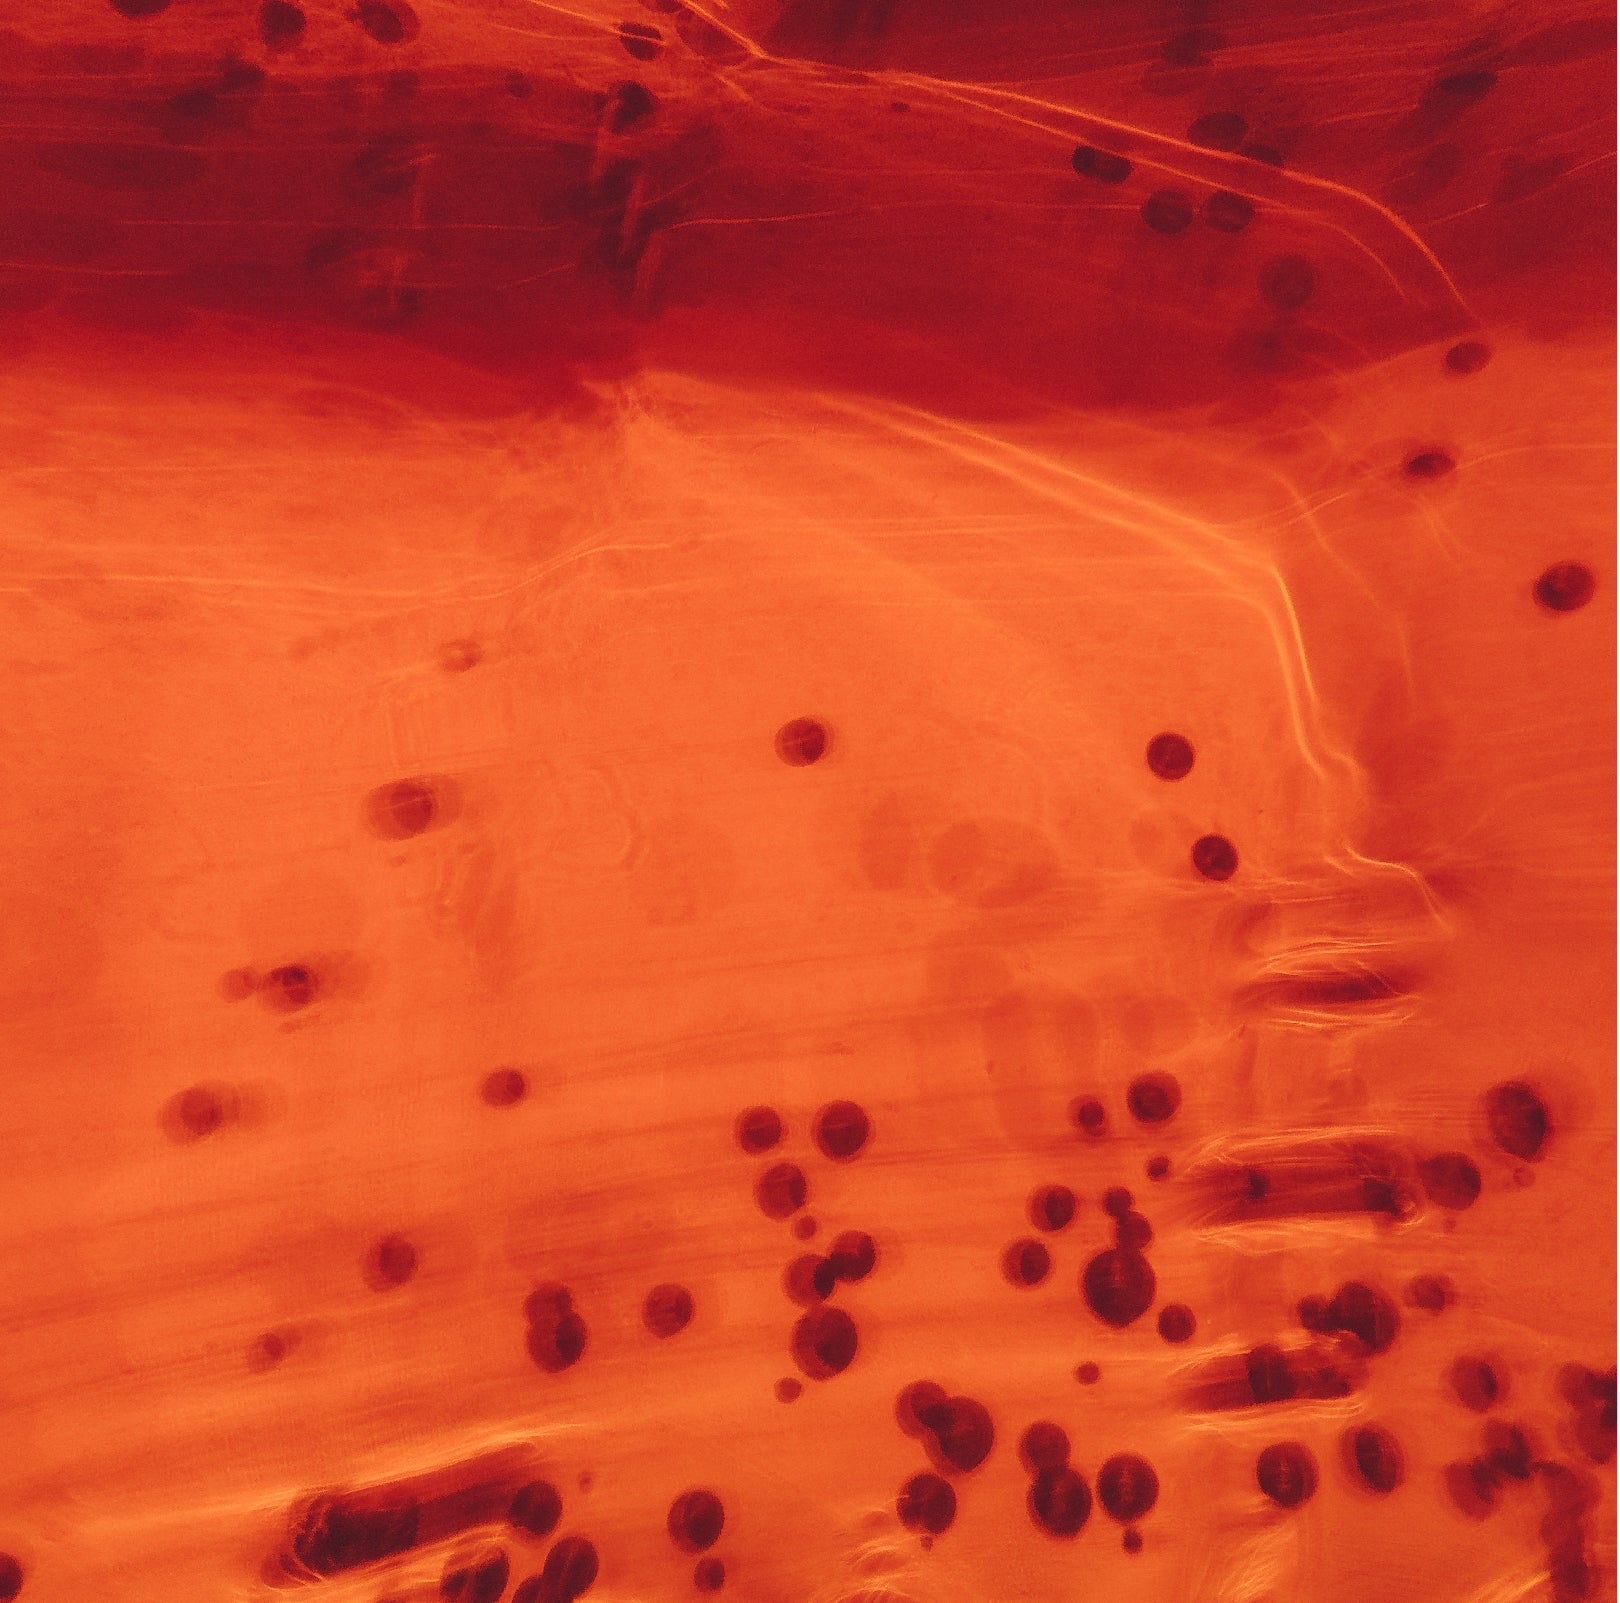

Mechanism of Action of Heme Iron

Heme iron is a bioavailable form that can be directly absorbed by intestinal mucosal cells without causing digestive tract irritation, offering high bioavailability.

Non-heme iron requires binding to transferrin within intestinal mucosal cells for absorption, making it susceptible to gastric acid secretion and resulting in an absorption rate of 5–8%. Heme iron, however, is absorbed directly by intestinal mucosal cells and is unaffected by gastric acid.